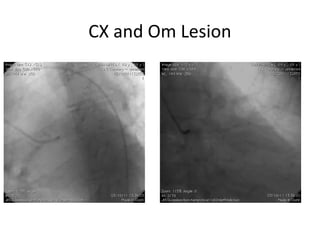

CX and Om Lesion

CX and OmLesion